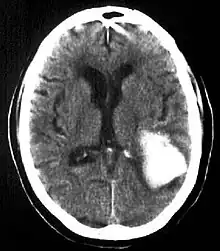

Intraparenchymal hemorrhage

CT-scan of intraparenchymal hemorrhage

Computed tomography (CT scan): A CT scan may be normal if it is done soon after the onset of symptoms. A CT scan is the best test to look for bleeding in or around your brain. In some hospitals, a perfusion CT scan may be done to see where the blood is flowing and not flowing in your brain.